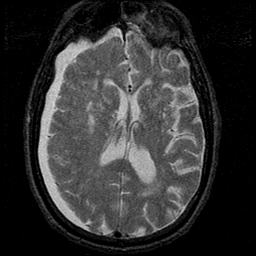

Subdural Hygroma,overlay -- Slice #27

[Home][Help][Clinical] Slice 27